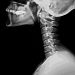

Primary brain tumors can be diagnosed using magnetic resonance imaging (MRI) or computerized tomography scan. The diagnosis may be confirmed with histopathology. Although doctors do not know the exact cause of primary brain tumors, they do know that certain risk factors can increase your risk. These include exposure to high-dose ionizing radiation, some diseases that affect the immune system, and medications that suppress the immune system.